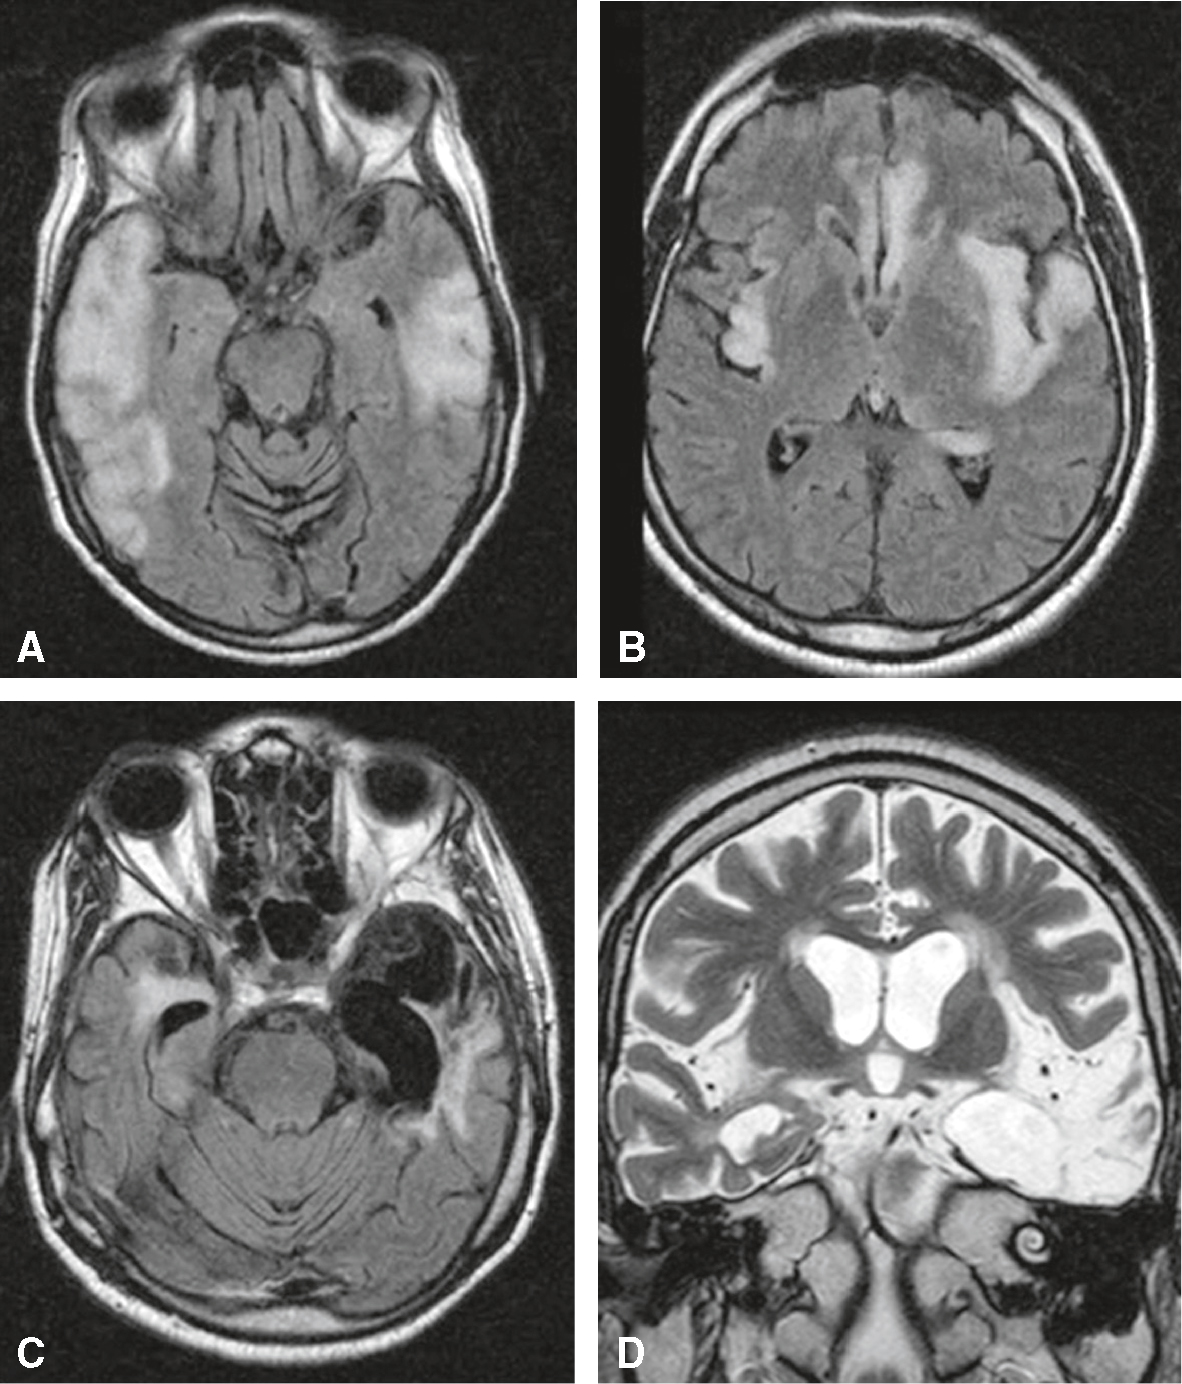

• L’IRM a une bonne sensibilité (90–100 % d’IRM pathologiques dans les 7 premiers jours), même dans les premières 24–48 heures (surtout en coupes coronales T1 avec injection de gadolinium et T2) (fig. 25.2). La limite vient de la faisabilité de l’examen en cas d’agitation d’un patient, qu’il faudra parfois sédater. Dans les formes méningées pures, l’IRM peut être normale. Des hypersignaux T2 apparaissent d’abord dans le pôle temporal antérieur et progressent vers le lobe temporal moyen et interne; ils sont typiquement de topographie bilatérale et asymétrique. La prise de contraste après injection de gadolinium (T1) témoigne de l’affinité de l’HSV pour le cortex hippocampique, parahippocampique et insulaire.

Fig. 25.2

Encéphalite herpétique (IRM).

En phase aiguë, hypersignal temporal bilatéral (A), temporal gauche, insulaire bilatéral et du gyrus cingulaire (B) sur les séquences T2/FLAIR. Aspect séquellaire de cavité porencéphalique temporale gauche en hyposignal sur les séquences axiales T2/FLAIR (C) et hypersignal sur les séquences coronales T2 (D).L'encéphalite herpétique est une infection rare mais grave du cerveau causée par le virus de l'herpès simplex (HSV). L'image obtenue par imagerie par résonance magnétique (IRM) montre des coupes transversales et coronales du cerveau, essentielles pour diagnostiquer cette condition. Les lobes temporaux sont souvent les premiers et les plus gravement touchés. Dans les images, on observe des anomalies de signal dans les lobes temporaux et frontaux, indiquant une inflammation et un œdème. L'image A montre des anomalies dans les lobes temporaux, alors que l'image B présente des zones de signal anormal plus supérieures. L'image C montre des anomalies similaires à un niveau différent et l'image D visualise les structures internes du cerveau, y compris les ventricules latéraux, avec des signes d'inflammation et de nécrose. Ces images sont cruciales pour diagnostiquer l'encéphalite herpétique car elles montrent les zones spécifiques du cerveau affectées par le virus. Les lobes temporaux sont souvent les plus touchés, ce qui peut entraîner des symptômes tels que des convulsions, des troubles de la mémoire et des changements de comportement. L'IRM est un outil essentiel pour détecter ces anomalies et confirmer le diagnostic. En résumé, les images IRM montrent des anomalies dans les lobes temporaux et frontaux, caractérisant une encéphalite herpétique.

- • Trois mois à un an après l’épisode initial, l’IRM montre souvent une atrophie d’un ou des deux noyaux amygdaliens, isolée ou associée à une atrophie hippocampique.

- • 472La présence d’hypersignaux T2 étendus dans les lobes temporaux en IRM persistant 1 à 2 mois après la phase aiguë est de mauvais pronostic.